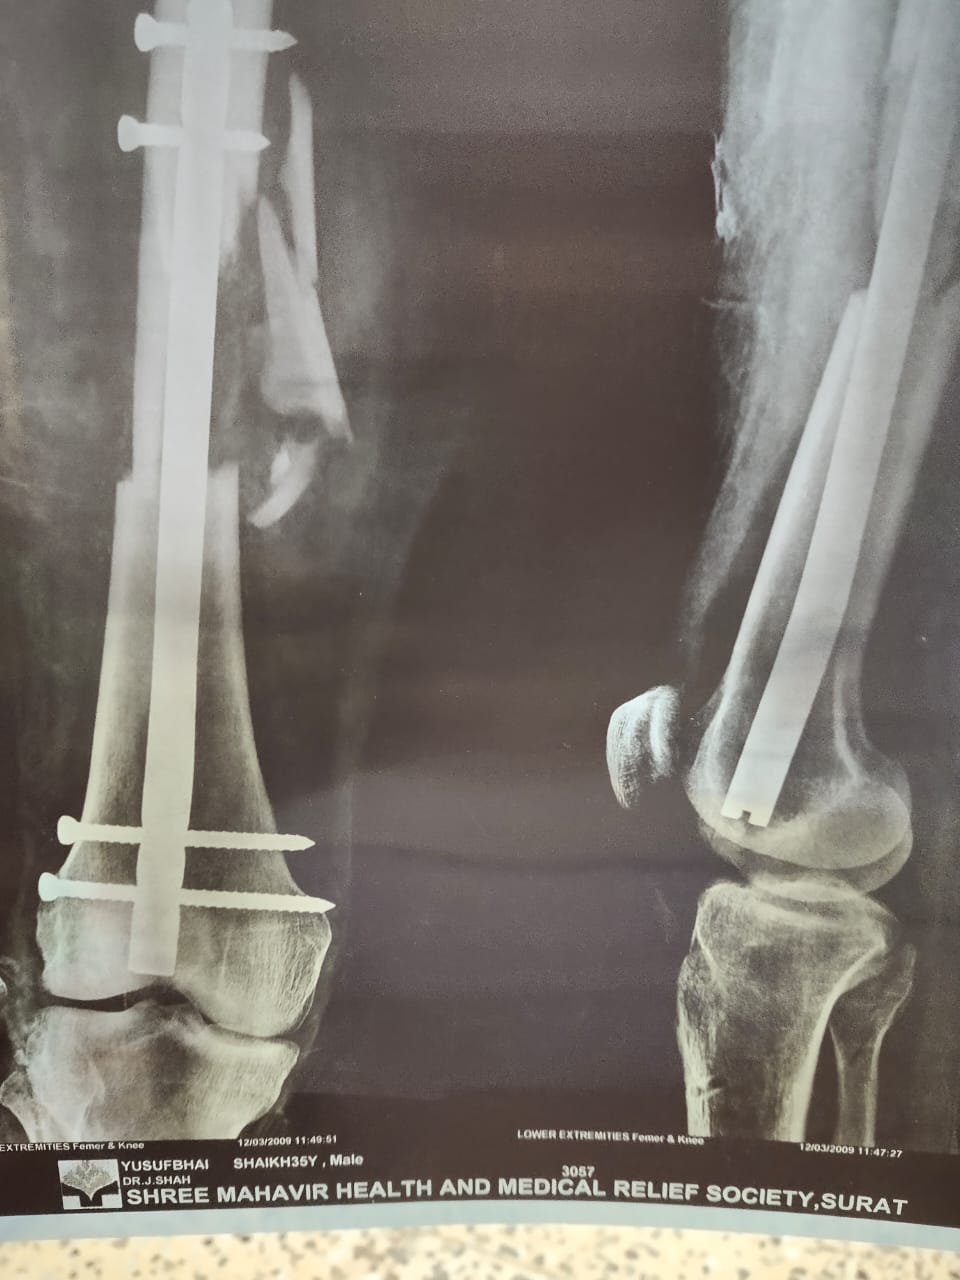

हमने इलियास से इस पूरी घटना के बारे में जानने के लिए कॉन्टैक्ट किया. उन्होंने बताया, “मैं डाभेल जाने के लिए 22 तारीख की सुबह निकला था और मैंने रास्ते में पड़ने वाले इस पेट्रोल पम्प पर पेट्रोल भरवाया. हाईवे पर गाड़ी चला रहा था तो इसी वजह से मैंने चश्मे और मास्क पहने थे. मेरा 2009 में एक एक्सीडेंट हुआ था जिसकी वजह से मैं अपने दाहिने हाथ से कुछ ठीक से पकड़ नहीं सकता हूं. मेरा ये हाथ हरकत तो करता है लेकिन उससे मैं कोई भी चीज़ पकड़ नहीं सकता. इसी वजह से मेरे दाहिने हाथ से कब नोट गिर गई मुझे पता नहीं चला. आपने अगर वीडियो देखा है तो आपको मालूम होगा कि मैंने अपने उलटे हाथ से जेब से पैसे निकाले और उन्हें दिए. इसी बीच मेरे अंगूठे में एक नोट फंस गई जिसका मुझे पता ही नहीं चला और वो नोट मेरे हाथ से गिर गई.”

इलियास से FIR के बारे में पूछने पर उन्होंने बताया, “मुझे वलसाड पुलिस स्टेशन में बुलाया गया था और पूछताछ की गई थी. तब मैंने उन्हें बताया कि मैं नवसारी नहीं गया था लेकिन हाईवे के रास्ते से मैं डाभेल ज़रूर गया था. मेरे कंधे के नीचे स्टील का रॉड डाला गया था जिसकी वजह से कभी-कभी मुझे दर्द होता रहता है और मुझे हर 2-3 महीने में डॉक्टर के पास चेक-अप करवाने के लिए जाना पड़ता है. उसके बाद वहां पर नवसारी पुलिस स्टेशन से कुछ लोग आए और मुझे नवसारी के रूरल पुलिस स्टेशन ले गए. वहां पर नवसारी के सरकारी हॉस्पिटल में ले जाकर मेरा चेक-अप करवाया गया. इसके बाद डॉक्टर ने साफ़ कर दिया कि मुझे कोई प्रॉब्लम नहीं है और कोरोना के कोई भी लक्षण नहीं हैं. मुझे तब तक इस मामले के बारे में कुछ मालूम ही नहीं था. उसके बाद मैंने अपने पैरालिसिस हो चुके हाथ के बारे में पुलिस को बताया तो उन्होंने भी माना कि मैंने जान-बूझकर नोट नहीं फेंका था. इसके बाद पेट्रोल पम्प के लोग भी वहां पर आए और उन्होंने मेरा हाथ देखा. सभी ने ये बात मान ली कि मेरे हाथ से नोट गलती से गिर गई थी. इसके बाद मुझे ज़मानत दे दी गई. मुझे डॉक्टर ने घर पर ही रहने के लिए कहा है और इसीलिए मैं अपने घर पर ही रहता हूं.” इलियास ने इस पूरी घटना के बारे में एक वीडियो रिकार्ड कर हमें भेजा है जिसमें आप उनके घायल हाथ को साफ़ देख सकते है.

इलियास के एक्सीडेंट के बाद उनके हाथों और कन्धों का एक्स-रे यहां देखा जा सकता है.